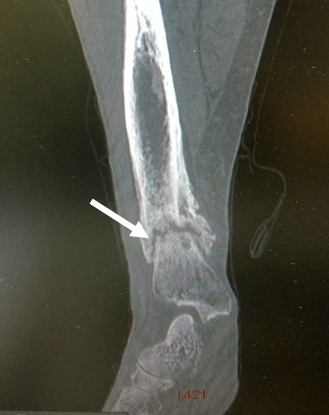

In June 2016 patient got right tibia fracture after fall from own height (fig.1), later patient suffered from restricted mobility because of fracture nonunion. She has been moving only by wheelchair for 3 months after fracture. Patient was able to move freely 7 months after the fracture. Neither phosphorus and calcium levels, nor BMD was measured.

Figure 1. МSCТ of the right femur: right tibia fracture in the lower third with signs of callus formation.